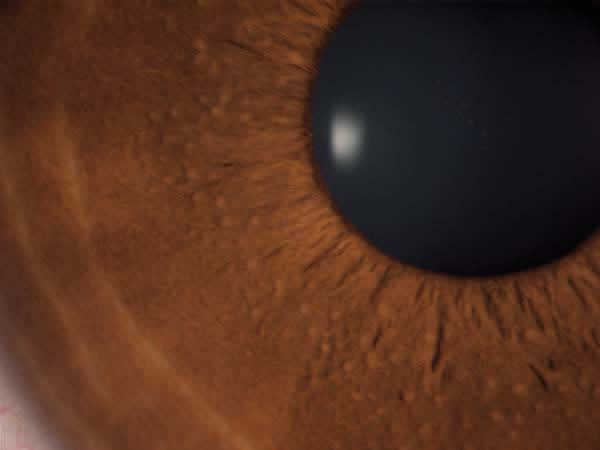

Figs. 2a y 2b: Mamelones menos pigmentados que en el anterior caso, también en reborde pupilar. Más dispersos. 2.º Caso clínico.

Figs. 2c y 2d: Detalles de mamelones a mayor aumento ojo derecho y ojo izquierdo. Los mamelones en este caso son del mismo tono del iris.